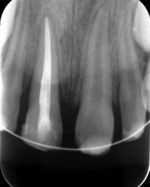

W celu replantacji ząb przemyto jałowym roztworem soli fizjologicznej. Za pomocą gazy korzeń oczyszczono z resztek ozębnej. Następnie umieszczono w żelu Elmex na 20 minut, aby spowolnić ewentualną następową resorpcję (ryc. 2).[3] Kanał został opracowany i wypełniony metodą kondensacji bocznej gutaperki oraz pastą AH PLUS poza jamą ustną. (ryc. 3). Po leczeniu endodontycznym ząb zabezpieczono materiałem Ketac-Fil. Wierzchołek korzenia nieco wygładzono. W znieczuleniu nasiękowym preparatem 4-proc. Ubistesin forte zębodół zbadano i przepłukano solą fizjologiczną. Ząb replantowano z delikatnym naciskiem, zwracając uwagę na zachowanie prawidłowych kontaktów zwarciowych (ryc. 4). Następnie założono ligaturę drucianą, włączając do unieruchomienia zęby 53, 12, 21, 22, 63 (ryc. 5). Wykonano kontrolne zdjęcie RTG (ryc. 6). Ze względu na długi okres przebywania zęba poza jamą ustną w niekorzystnym środowisku oraz wakacyjny wyjazd pacjentki, unieruchomienie pozostawiono na pięć tygodni.